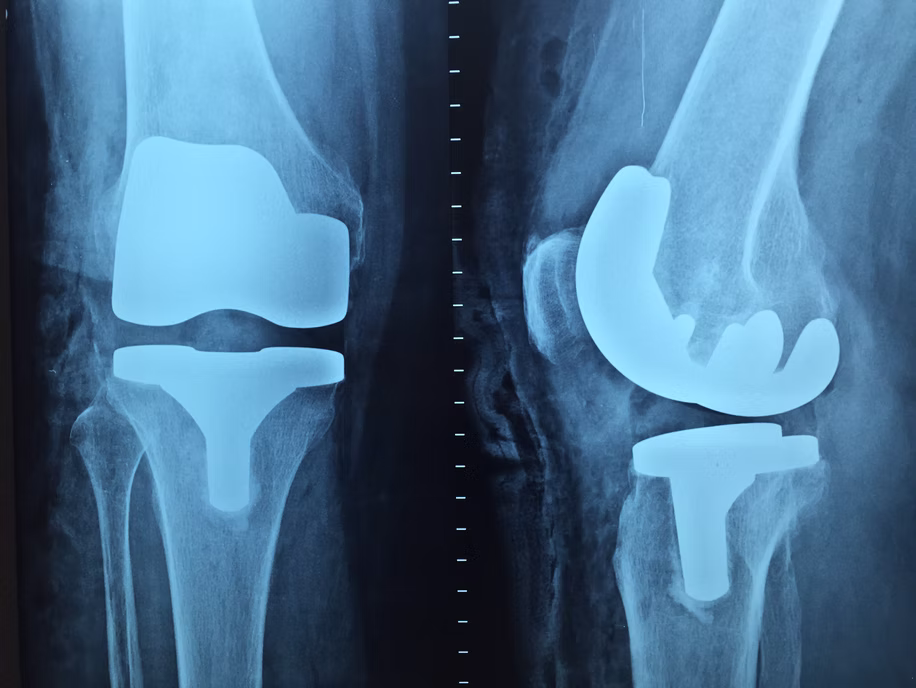

ОПЕРАЦИЯ ПО ЗАМЕНЕ КОЛЕННОГО СУСТАВА

Также известная как артропластика коленного сустава или тотальное эндопротезирование, эта операция проводится для устранения боли и восстановления подвижности колена. Она рекомендуется пациентам, страдающим артрозом, разрывом мениска, повреждением хряща или дегенеративными заболеваниями суставов.